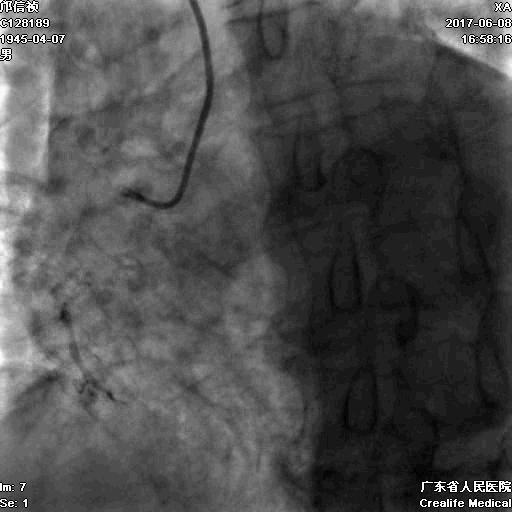

第二步:处理LCX

Fielder XT-A,Gaia First ---在微导管支撑下通过闭塞病变

LCX植入支架

2.0*10mm球囊

2.75*22mm药物支架